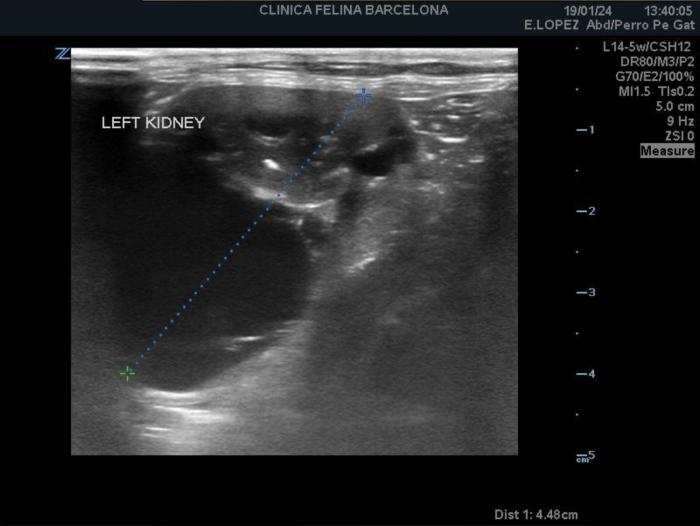

En la ecografía abdominal se visualizaron los dos riñones con contorno irregular. Tanto en la corteza como en la médula de ambos riñones se distinguieron múltiples estructuras redondeadas y anecoicas, de tamaño variable, compatibles con quistes (Figura1 y 2).

La ecografía es la herramienta diagnóstica más práctica en individuos adultos. En la fase inicial de la enfermedad, resulta complicado identificar quistes de pequeño tamaño, sobre todo si su diámetro es inferior a 2 mm (3). La sensibilidad aumenta en función de la edad, siendo del 75 % cuando se realiza a las 16 semanas de edad y del 91 % a las 36 semanas. La especificidad se estima del 100 %, aunque depende sobre todo de la experiencia del ecografista (1). Se ha visto que la ausencia de quistes en la ecografía a los 6 meses de edad se asocia con la ausencia de ERP en la necropsia (4).

Ecográficamente, los quistes se visualizan como estructuras redondas u ovaladas, de tamaño variable (desde menos de 1 mm hasta más de 1 cm), con la pared fina y contenido anecoico con fuerte refuerzo acústico posterior. La mayoría se localizan en la corteza y en la unión corticomedular de uno o ambos riñones. Con el paso del tiempo, los quistes aumentan en número y volumen, sustituyendo el parénquima normal e incluso llegando a deformar el contorno renal. En algunos casos se pueden desarrollar quistes en el hígado y/o páncreas (4)(6)(8) (Figura 4). En nuestro paciente, ecográficamente se observaron ambos riñones irregulares y con quistes, sin lesiones en hígado ni tampoco en páncreas.